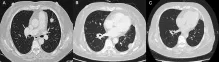

为了尽快控制病情,张阿姨接受了完全切除术,然而不幸的是,手术后不久就出现了转移,并且由于她的生长抑素受体表达极低,生长抑素类似物和肽受体放射性核素治疗等常规手段均无法应用,只能不断尝试各类化疗药物。让医生束手无策的是,在使用了包括卡铂、依托泊苷、卡培他滨、替莫唑胺、紫杉醇在内的多种化疗药物,以及依维莫司和阿特珠单抗等治疗方案后,肿瘤仍在疯狂增长,张阿姨病情持续恶化,出现无数皮下结节、左侧胸膜转移、多发性骨转移和脑转移等严重状况...

基于这一发现,医疗团队迅速调整策略,为张阿姨启用第一代原肌球蛋白受体激酶抑制剂恩曲替尼(600 毫克,每日一次)进行治疗。

奇迹就这样发生了,治疗仅1个月迅速起效,张阿姨所有转移性肺病灶实现完全缓解。更令人欣喜的是,从开始接受恩曲替尼治疗至今,已持续获益至少一年,目前治疗仍在顺利进行中。